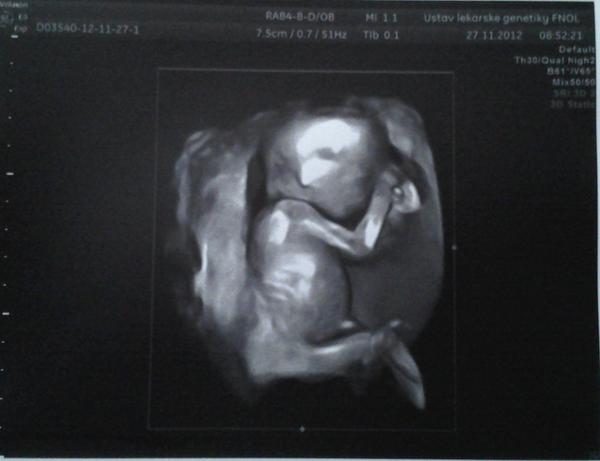

Jinak včera jsme byli na kontrole na genetice a řekla bych, že dopadla perfektně (ale pořád nechceme nic zakřiknout!) 🙂 Miminku se daří dobře a podle všeho je zdravé 🙂 A zatím to vypadá na holčičku. Dr. říkal, že tam toho pindíka prostě nevidí, spíš ukazoval tu čárku 😀 Ale bereme to s rezervou 🙂 Hlavně ať je vše v pořádku 🙂